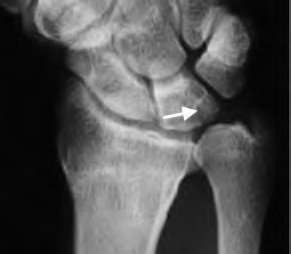

A 35-year-old woman reports wrist pain after a fall onto an outstretched hand. On exam, she has focal tenderness over the wrist snuffbox. A radiograph and CT image are shown in Figures A and B. What is the proper treatment of her injury?